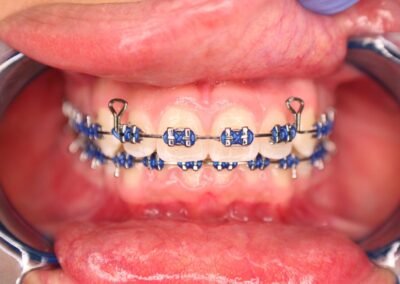

Many of us are not born with picture perfect teeth. For the straight teeth and alignment many people are searching for, braces is a common and effective treatment. Precision Dental Care uses the latest X-Ray technology to trace and model your teeth for your unique dental needs. From crooked teeth to alignment issues, braces can solve a variety of oral concerns.

Dr. Fonseca has years of experience so you can count count on the results you want. Trust our team to guide you through the experience every step of the way for a comfortable fit.